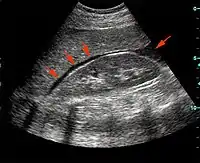

FAST is most useful in trauma patients who are hemodynamically unstable. A positive FAST result is defined as the appearance of a dark ("anechoic") strip in the dependent areas of the peritoneum. In the right upper quadrant this typically appears in Morison's Pouch (between the liver and kidney). This location is most useful as it is the place where fluid will collect with a supine patient. In the left upper quadrant, blood may collect anywhere around the spleen (perisplenic space). In the pelvis, blood generally pools behind the bladder (in the rectovesicular space). A positive result suggests hemoperitoneum; often CT scan will be performed if the patient is stable[18] or a laparotomy if unstable. In those with a negative FAST result, a search for extra-abdominal sources of bleeding may still need to be performed.